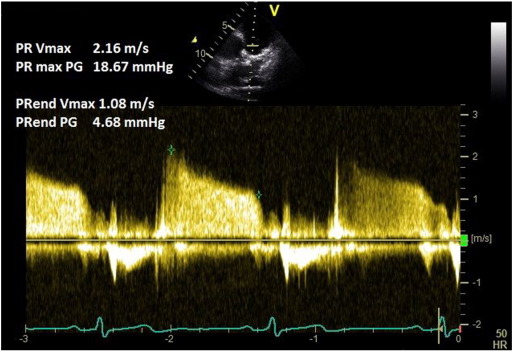

Tissue Doppler imaging (TDI) is used on the RV free wall in the apical 4-chamber view, and tricuspid annular systolic myocardial (Sm ) velocity is recorded. The maximal Sm velocity and the Sm VTI are then measured (Fig. 6 ). Sm velocity < 12 cm/s and Sm VTI < 2.5 are highly suggestive of elevated PASP [23] .

Fig. 6.

RV tissue Doppler method for assessing pulmonary pressure.

6.2. Common pitfalls

This method correlates well with TR measured PASP but is yet to be fully validated against the gold standard-invasive right heart catheterisation [23]  and [24] . Although the technique helps to identify patients with pulmonary hypertension, it cannot accurately quantify pulmonary artery pressure.